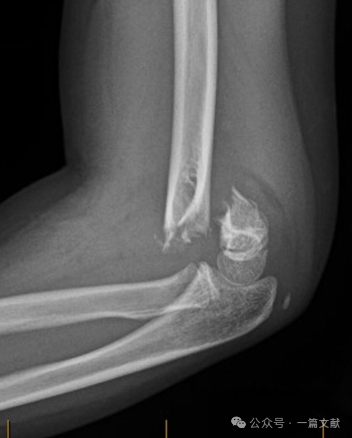

II. Imaging Studies: Plain radiographs are usually sufficient. AP and lateral views of the elbow are required. Obtain ipsilateral forearm/wrist radiographs to assess for associated injuries. Evaluate for the posterior fat pad sign in nondisplaced fractures (indicated by arrow).

Alignment on Lateral Radiograph:

* Anterior Humeral Line (AHL): Should pass through the ossification center of the capitellum.

* Capitellar Anterior Angle: 30-40 degrees.

* Lateral Capitellohumeral Angle (LCHA): Should be less than 69 degrees.

* Posterior Fat Pad Sign: Highly suggestive of fracture (whereas an anterior fat pad sign can be seen without fracture).